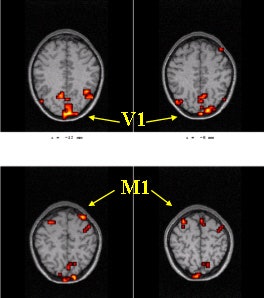

The areas of investigation were the left and right primary motor cortices (M1) and the primary visual cortex (V1). Above, a baseline fMRI scan during a visually cued motor task. Below, the same areas scanned after caffeine. Significant changes were seen in the signal change of the BOLD response. Images courtesy of Todd Parrish, Ph.D.

The average BOLD signal amplitude response was determined from three areas of investigation, including the left and right primary motor cortex and the primary visual cortex. Additional analysis was done to measure the signal-to-noise ratio (SNR) in the nonactivated BOLD data, both before and after treatment.

After the administration of caffeine, the average percentage signal change of the BOLD response, relative to baseline, showed significant changes in both motor and visual areas, with the motor region exhibiting a 37% signal change. In addition, there was a notable decrease in the SNR following caffeine, with an average decrease of 4.4%. Finally, the average perfusion level decreased by 11%-13% without a change in performance as measured by reaction time, the group concluded.